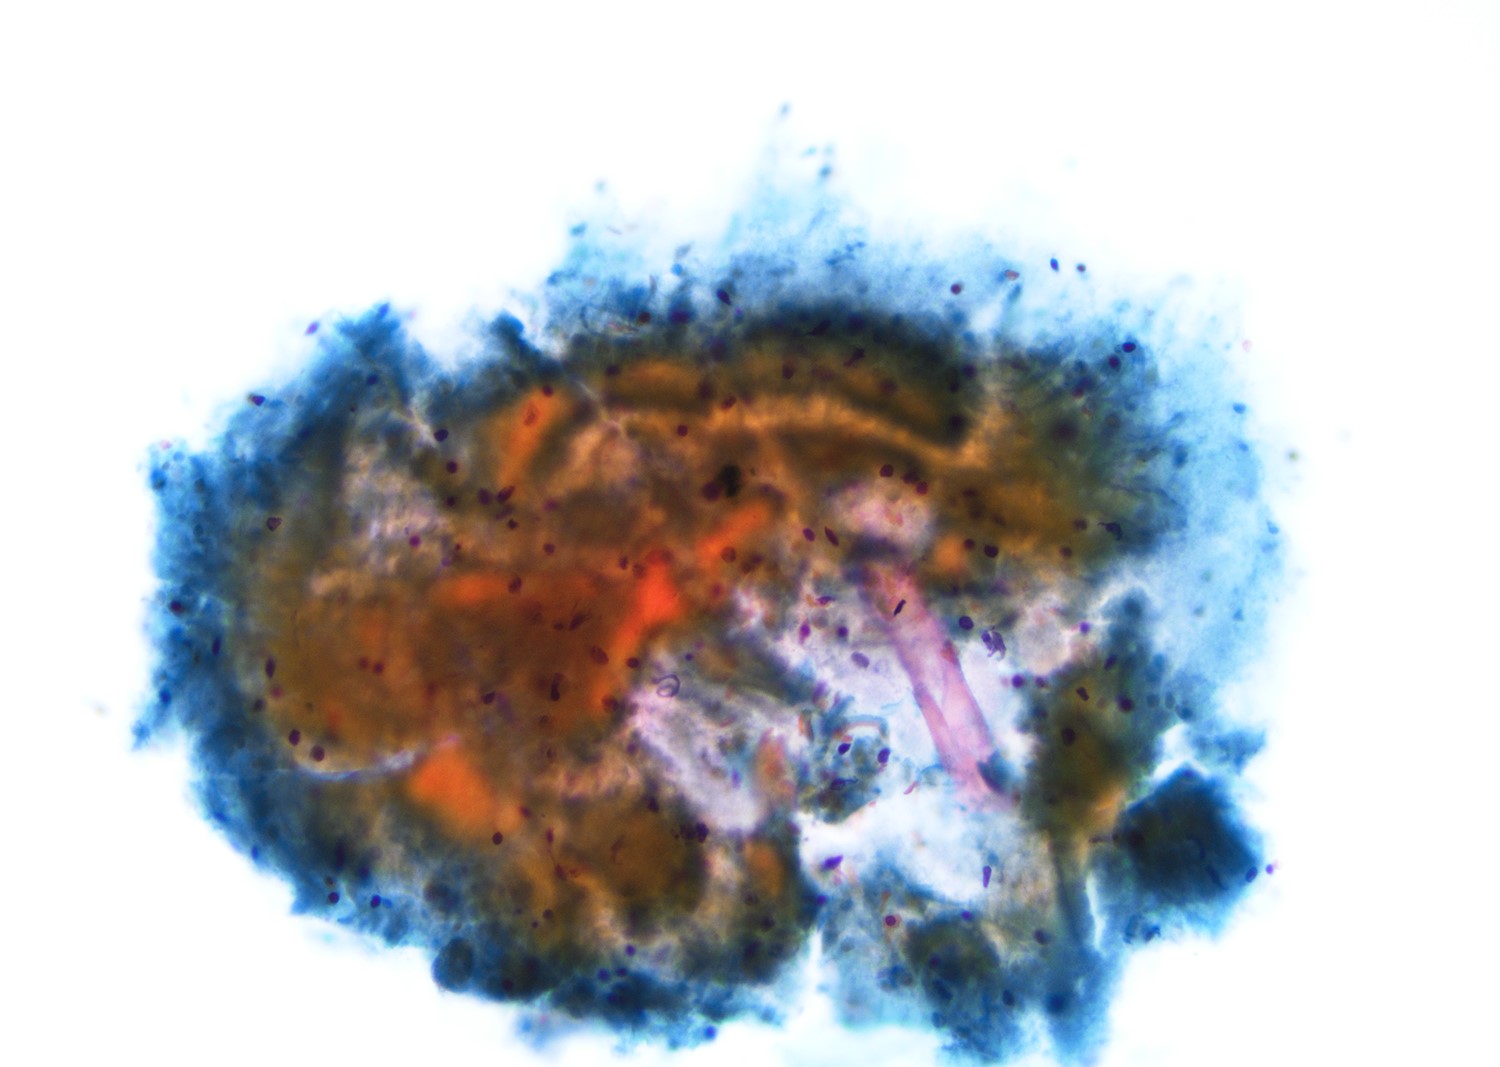

Gross description

- Cystic structure containing a serous clear watery straw colored fluid with smooth and glistening inner lining

Microscopic (histologic) description

- Most cases show a unilocular cyst with a thin stratified squamous lining

- Ciliated, cuboidal or columnar epithelial lining is seen in rare cases

- Epithelium is surrounded by dense polymorphous lymphoid tissue with germinal centers and sinusoidal spaces

- Lymphocytes frequently permeate the epithelial cyst lining cells

Microscopic (histologic) images